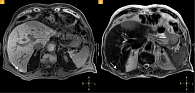

Рис. 2. Меланинсодержащий метастаз: А – на бесконтрастных Т1-ВИ с жироподавлением виден гиперинтенсивный очаг (стрелка); Б – этот же очаг (стрелка) имеет гиперинтенсивный сигнал на Т2-ВИ

Гиперинтенсивный сигнал в очагах поражения печени, как на бесконтрастных Т1-ВИ, так и на Т2-ВИ, у пяти больных мог быть обусловлен отложением меланина (рис. 2А, 2Б).

В свою очередь, один раз проведенное МРТ-исследование может быть проконсультировано разными специалистами. В частности, при МРТ брюшной полости используют стандартные импульсные последовательности Т1 и Т2 взвешенных изображений. Гиперинтенсивный очаг печени на бесконтрастных изображениях, как на Т1-ВИ, так и на Т2-ВИ, может быть обусловлен отложением меланина и является патогномоничным признаком для метастазов меланомы в дифференциальной диагностике очагового поражения печени [21, 22].

При сравнении метастазов в печени кожной и увеальной меланом было отмечено, что у пациентов с УМ более высокая экспрессия антигена MelanA, более высокое содержание меланина в клетках [23]. В этой связи логично предположить, что повышение МР-сигнала на Т1-ВИ в очаговых образованиях печени при наличии в анамнезе УМ будет патогномонично для метастазов УМ. И хотя данная сигнальная характеристика встречалась только у 5 (38,5%) из 13 обследованных нами пациентов с метастазами, она имеет решающее значение при обнаружении и дифференциальной диагностике метастатических очагов меланомы.